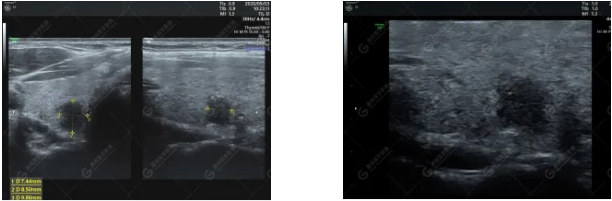

甲狀腺右側(cè)葉探及低回聲結(jié)節(jié),大小約7mm×9mm×10mm,邊界欠清,形態(tài)欠規(guī)則,縱橫比>1,內(nèi)可見少許點(diǎn)狀強(qiáng)回聲,后方回聲無明顯變化。其下方另可探及一低回聲結(jié)節(jié),大小約4mm×3mm×4mm,縱橫比>1,邊界欠清,內(nèi)回聲欠均勻。

彩色多普勒顯示:甲狀腺右側(cè)葉較大結(jié)節(jié)周邊可見少許細(xì)條狀血流信號(hào),較小結(jié)節(jié)未見明顯血流信號(hào);余腺體內(nèi)未見異常血流信號(hào)。

二維超聲:右側(cè)葉探及低回聲結(jié)節(jié),邊界欠清,形態(tài)欠規(guī)則,縱橫比>1,內(nèi)可少許細(xì)點(diǎn)狀強(qiáng)回聲,后方回聲無明顯變化。

CDFI:結(jié)節(jié)周邊可見少許細(xì)條狀血流信號(hào),內(nèi)部未見明顯血流信號(hào)。